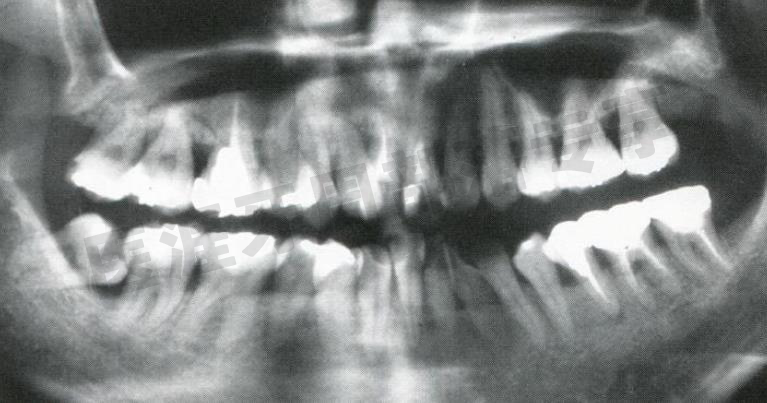

怎么选洁牙器械5个要点带你学习器械洁牙_https://www.jmylbn.com_新闻资讯_第41张

护理时的牙周精密检查(2007 年4 月)

部分牙周袋深度达 6mm 且有出血。是否是炎症复发的迹象?对上下颌左侧 6 进行了清创术。

怎么选洁牙器械5个要点带你学习器械洁牙_https://www.jmylbn.com_新闻资讯_第42张